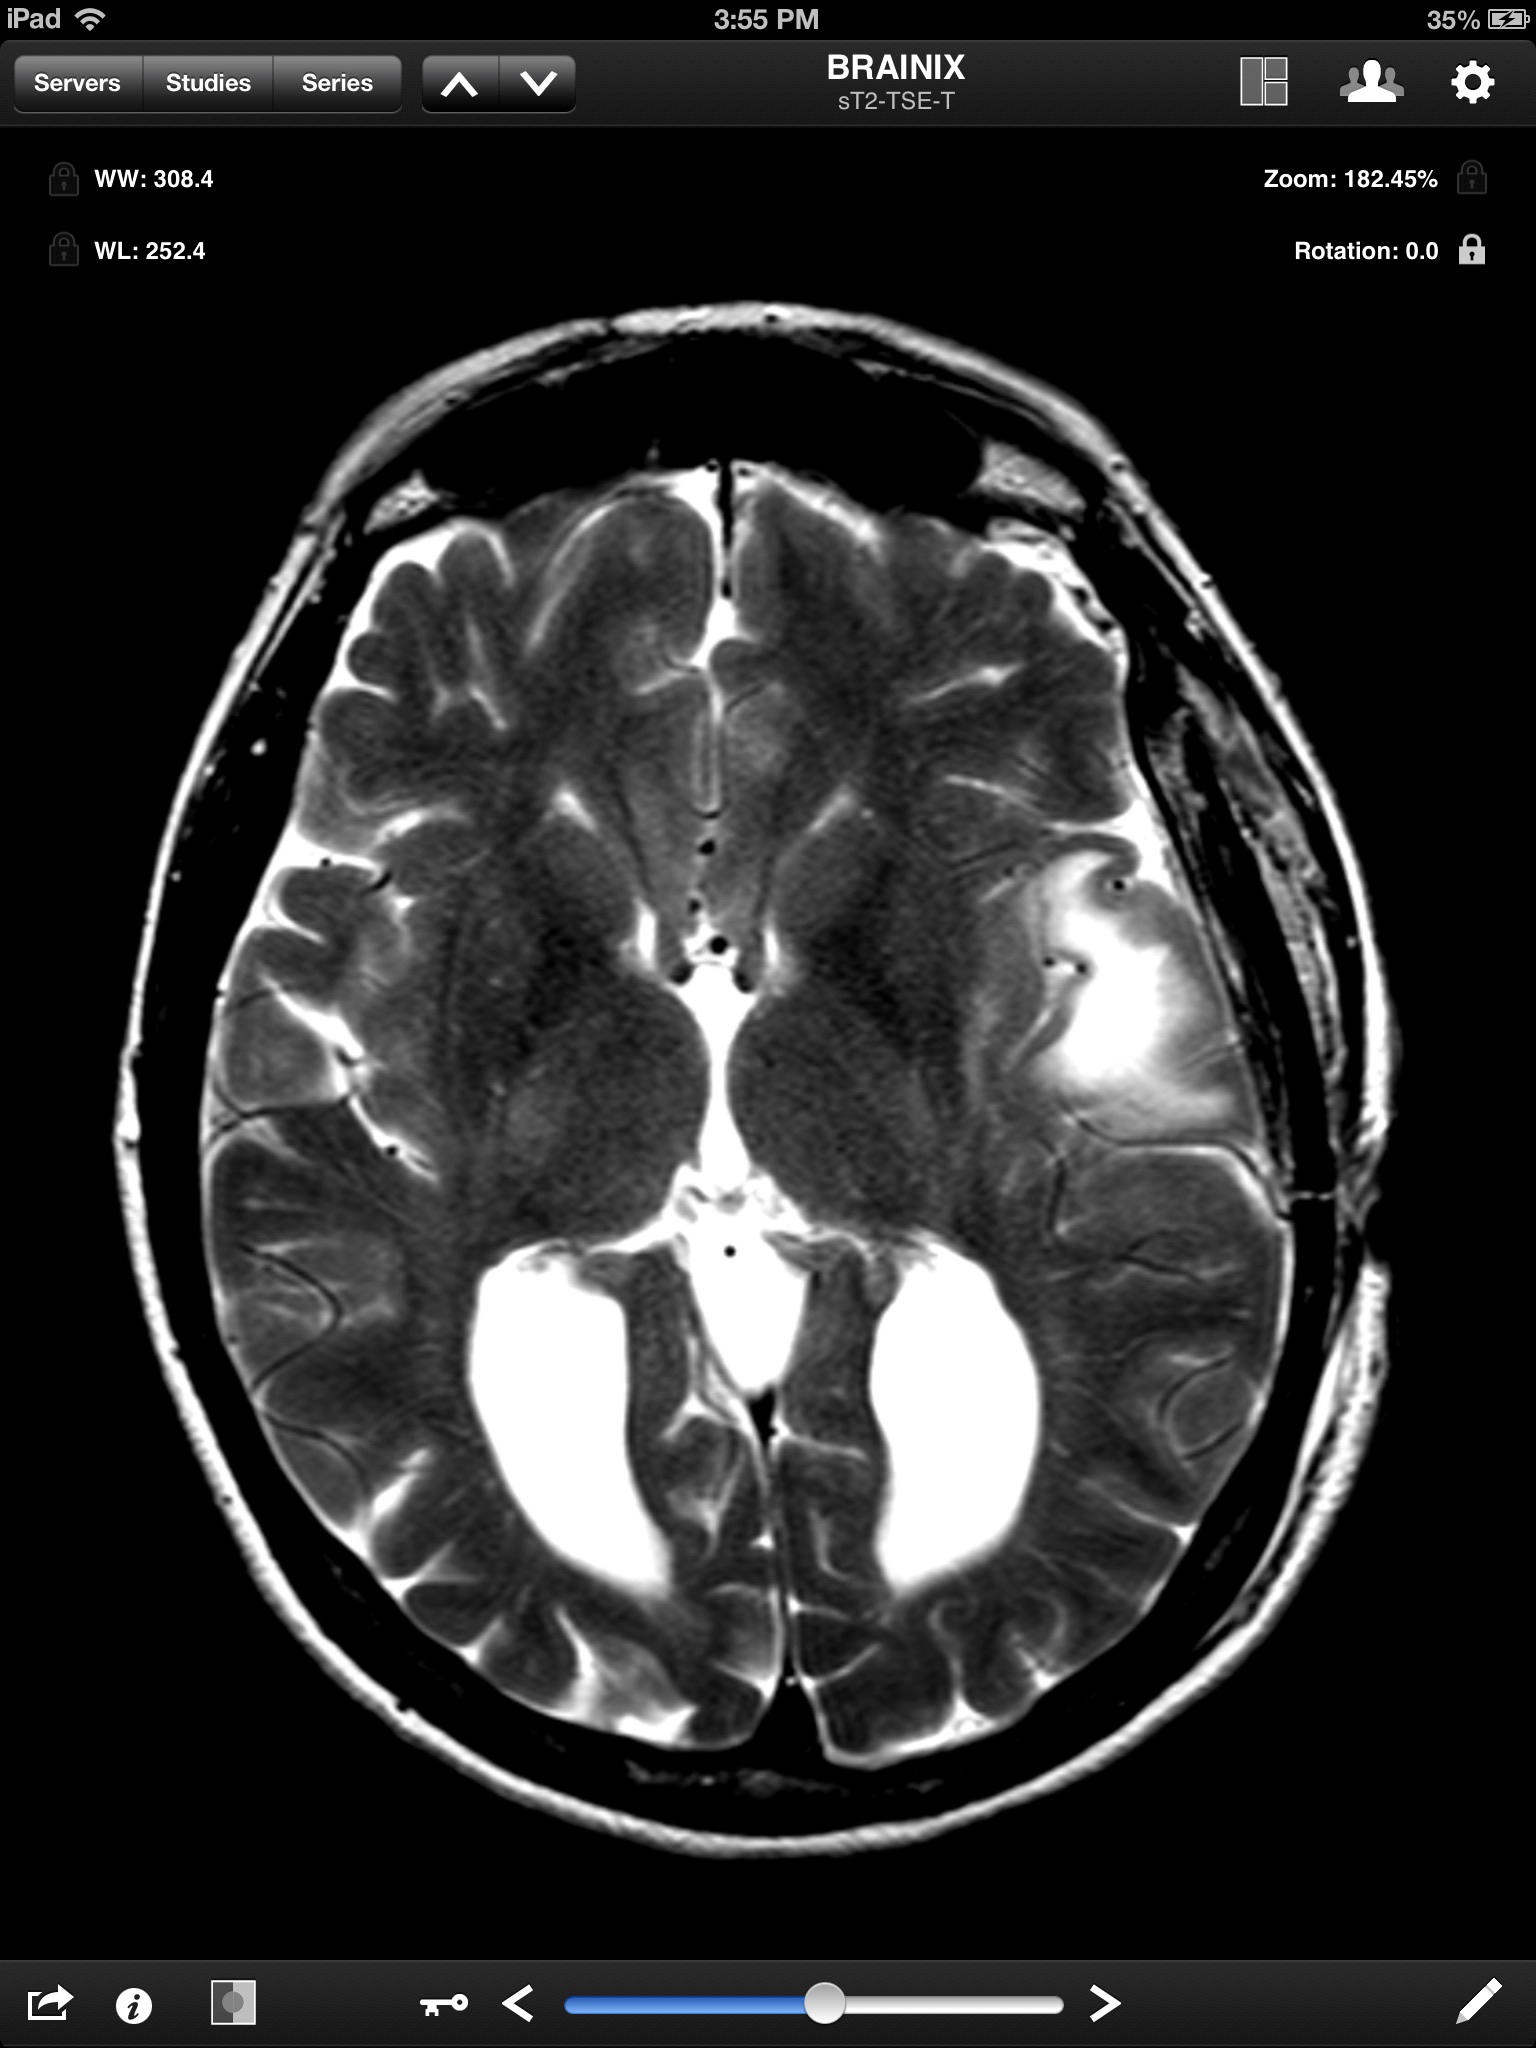

Jack Imaging Medical Image Viewer, a medical image viewer for the iPad, is the latest in medical imaging innovation! It supports reading the DICOM format ( the industry standard for storing medical images) and the most common imaging modalities. Jack Imaging Medical Image Viewer supports fast user interaction for the most common actions, including zoom, pan, windowing (brightness and contrast adjustment) using multitouch gestures.

- View DICOM images

- View transformation (zoom, pan) using two finger multi-touch

- Adjust window width & level using one finger drag

- Full image resolution. Images will NOT be scaled down to 1024x1024 only.

- View the full image intensity window.

- Full GPU optimized rendering. Window operations are FAST and responsive.